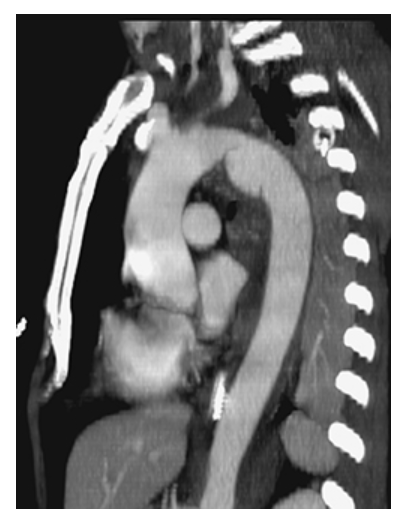

Aortic Coarctation. CTA sagittal oblique MPR of the chest shows severe narrowing in a different patient.